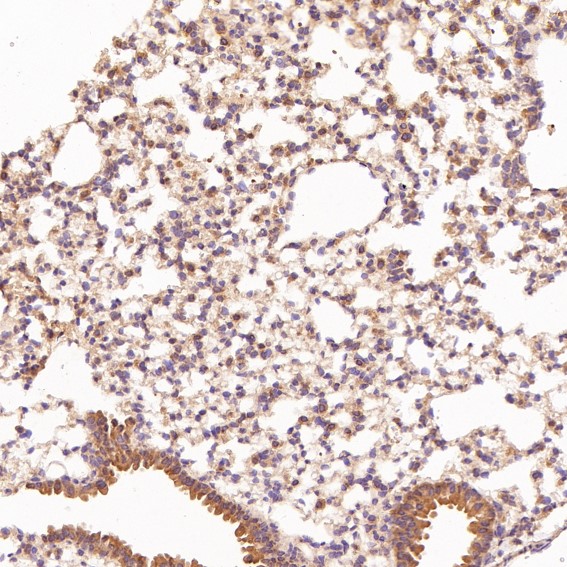

Immunohistochemical analysis of paraffin-embedded Mouse lung, using the Antibody at 1:200 dilution.